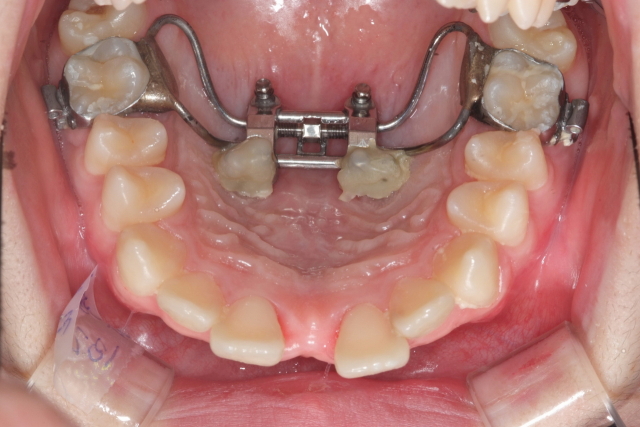

위 두 장은 MSE 시술 전후 입천장 모습. 위턱뼈가 벌어지면서 입천장이 확연히 넓어졌다. 이후 치아 배열을 하는 교정이 진행된다. 최종석치과의원 제공 위 두 장은 MSE 시술 전후 입천장 모습. 위턱뼈가 벌어지면서 입천장이 확연히 넓어졌다. 이후 치아 배열을 하는 교정이 진행된다. 최종석치과의원 제공